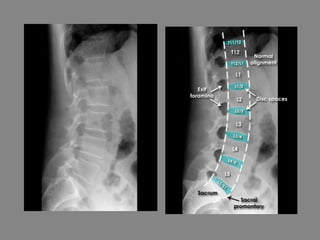

Thoracolumbar spine - Systematic approach

• Lateral and AP

• Coverage - The whole spine is visible on both views

• Alignment - Follow the corners of the vertebral bodies from one

level to the next

• Bones - The vertebral bodies should gradually increase in size

from top to bottom

• Spacing - Disc spaces gradually increase from

superior to inferior - Note: Due to magnification

and spine curvature the vertebral bodies and discs

at the edges of the image can appear larger than

those in the centre of the image

• Soft tissues - Check the paravertebral line (see AP

image below)

• Edge of image - Check the other structures visible

Thoracic spine - Systematic approach

• Alignment - Vertebral body alignment is

assessed by carefully matching the anterior

and posterior corners of the vertebral bodies

with the adjacent vertebra

• Bones - Gradual increase in vertebral body

height from superior to inferior

• Spacing - Disc spaces gradually increase in